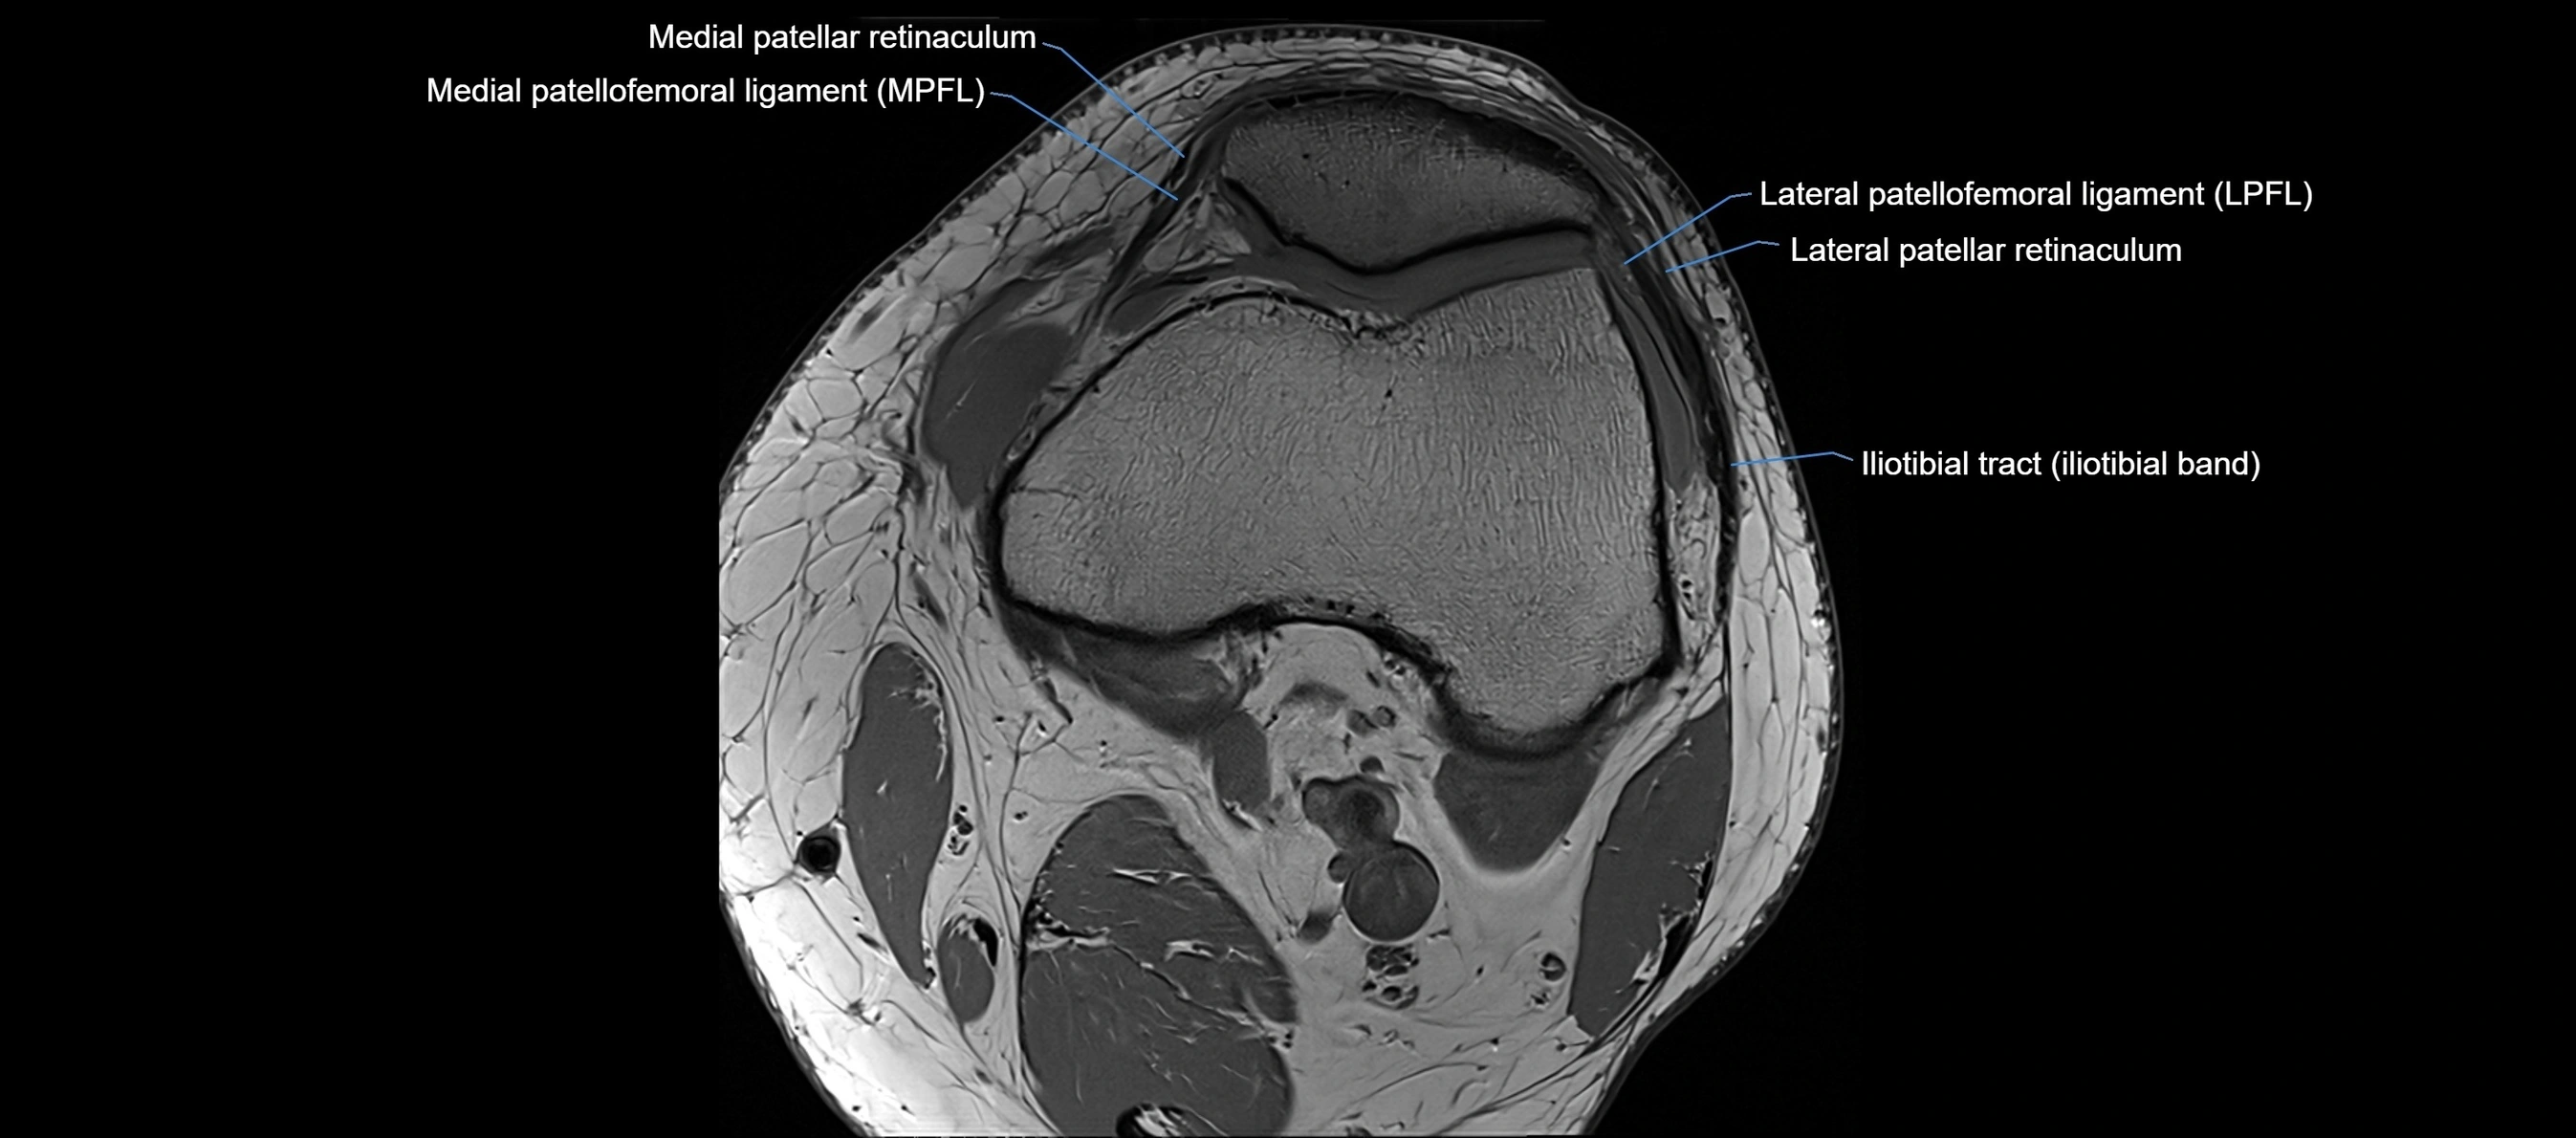

MRI Appearance

T1-weighted images:

• Normal ACL appears as a low-signal band-like structure crossing the intercondylar notch

• Surrounded by intermediate signal synovial fluid and fat planes

T2-weighted images:

• Normal ACL remains low signal

• Partial or complete tears appear as discontinuity, increased signal, or fiber laxity

STIR (Short Tau Inversion Recovery):

• Normal ACL shows dark low signal

• Acute injury shows bright hyperintensity due to edema and hemorrhage

Proton Density Fat-Saturated (PD FS):

• Normal ACL: dark, low-signal band

• Tears: bright intraligamentous hyperintensity, discontinuity, or abnormal course

MRI images

image